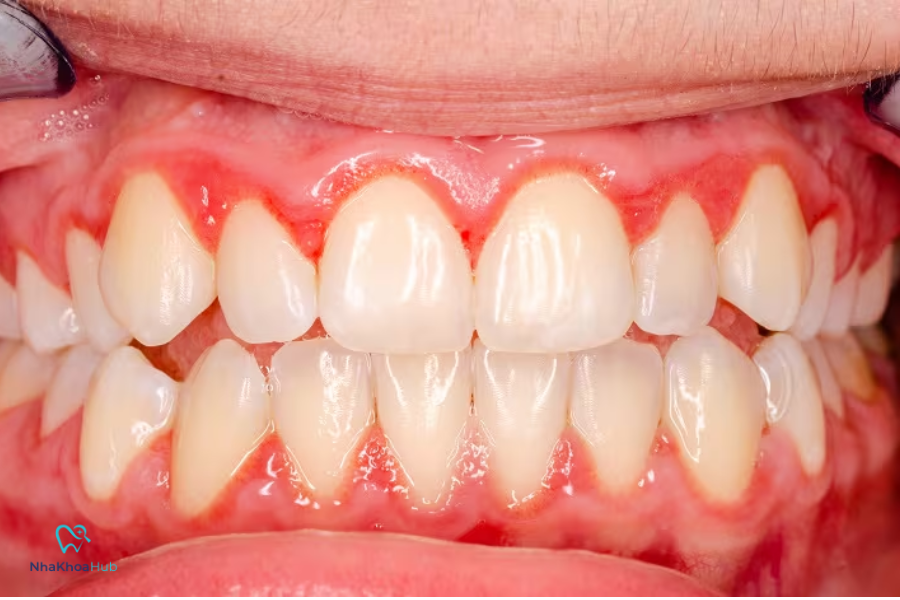

Dấu hiệu và triệu chứng nhận biết viêm nướu

Các dấu hiệu viêm nướu chân răng điển hình bao gồm:

- Nướu sưng đỏ, mềm, dễ chảy máu khi đánh răng hay dùng chỉ nha khoa.

- Hơi thở có mùi hôi dai dẳng dù đã vệ sinh răng miệng.

- Tụt nướu làm lộ chân răng.

- Ê nướu răng.

- Xuất hiện mủ ở kẽ nướu và răng.

- Cảm giác đau, khó chịu khi nhai.

Một nghiên cứu của National Institute of Dental and Craniofacial Research (NIDCR) cho thấy, hầu hết các ca viêm nướu giai đoạn đầu không gây đau, khiến người bệnh chủ quan và dễ bỏ qua các dấu hiệu sớm này.